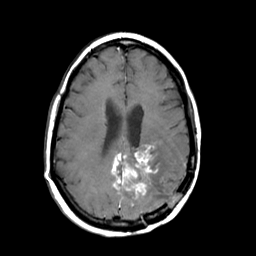

MR Study #3 -- Slice #34